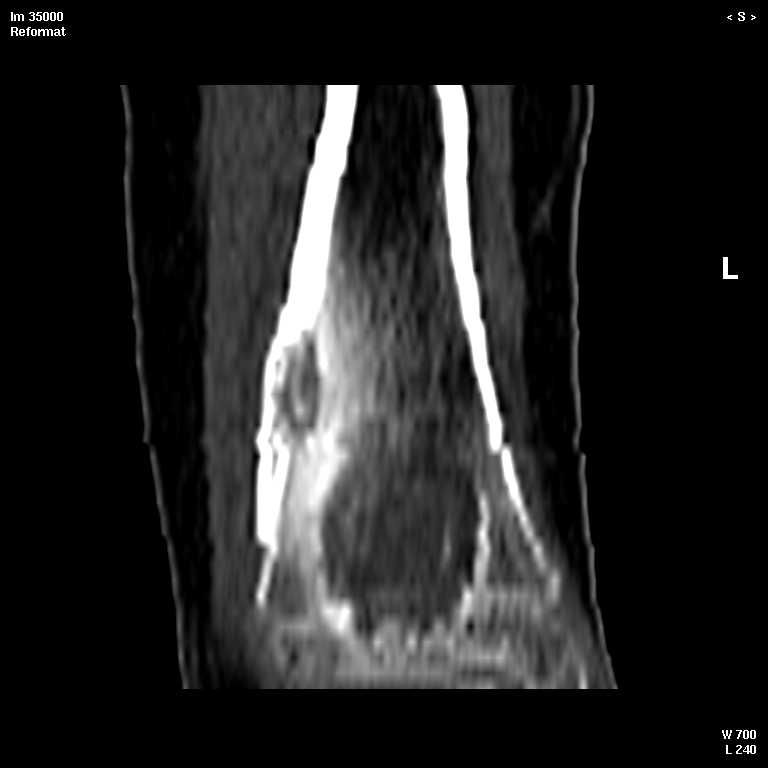

С подозрением на хондрому большеберцовой кости левой голени выполнена компьютерная томография. На серии томограмм получены изображения дистальных отделов левой голени. В дистальном метафизе на уровне нижней трети по латеральному краю определяется кортикальный очаг деструкции размерами 1,3x0,5x0,8 см. На уровне очага деструкции отмечается истончение кортикального слоя, без признаков его разрушения. Кость на уровне очага вздута. Структура окружающих мягких тканей не нарушена, объемных образований не определяется. Крупные нервные стволы и просветы крупных сосудов хорошо дифференцируются. Кожа и подкожно-жировая клетчатка не изменены.Заключение: КТ - признаки кортикального остеолитического очага деструкции в дистальном отделе метафиза левой большеберцовой кости без признаков разрушения кортикального слоя (остеогенная саркома?).19.11.2002 г. осмотрена онкологом, выставлен диагноз: саркома левой большеберцовой кости?Лабораторные исследования: - ОAK от 06.11.2002 г. - L - 11,3х109; эр. - 4,47хЮ12; НЬ - 117 гр./л; Ht - 33,6%; тр. -208x109; СОЭ - 38 мм./час, э-1; п-7; с-55; м-4; л-33.В отделении детской онкологии 11.12.02 выполнена операция: секвестр-некрэктомия н/3 левой большеберцовой кости.Послеоперационный период без осложнений.Проведено лечение. Линкомицин 150 мгхЗ р./д., обезболивание (анальгин, димедрол). Швы сняты 23.12.02, заживление первичным натяжением.Получен результат гистологического исследования: хронический остеомиелит. Данных за онкопроцесс нет.На приеме врача ортопеда поликлиники с жалобами на усиление болевого синдрома 03.01.03. Наложена задняя гипсовая лангета. Назначен противовоспалительная терапия, препараты Са и кальцийтониновые препараты. На фоне проводимого лечения болевой синдром купировался. На серии рентгенограмм (январь-февраль-март) На нижней трети левой большеберцовой кости наличие дополнительного кортикального очага диструкции с размерами 1.5x0,5 см., в динамике отмечается увеличение в размерах.С подозрением на рецидив хронического остеомиелита большеберцовой кости левой голени выполнена компьютерная томография.19/03/2003 На серии томограмм получены изображения дистальных отделов нижней трети левой голени и мягких тканей.В метафизе определяется очаг деструкции с четкими, неровными контурами, неоднородной структуры, за счет костных балок, размерами 1.8x1.8x2,4 см, плотностью 29 ед Н.В дистальном методиафизе. по латеральному краю, определяется кортикальный очаг деструкции, размерами 0,6x0,5x2,0 см, неоднородной структуры, за счет наличия фиброзных и костных балок, кортикальный слой истончен, без признаков разрушения.Структура окружающих мягких тканей не нарушена, объемных образований не определяется. Крупные нервные стволы и просветы крупных сосудов хорошо дифференцируются.Кожа и подкожно-жировая клетчатка не изменены.ЗАКЛЮЧЕНИЕ:КТ-картина состояния после операции. Формирование постоперационной, внутрикостной кисты. КТ-признаки объемного образования нижней трети левой большеберцовой кости, вероятнее всего фиброзная дисплазияРЕКОМЕНДАЦИИ: МРТ левого голеностопного сустава с захватом нижней трети голени.Лабораторные исследования: OAK от 05.03.2003 г. - L v 7.0х109; эр. - 4,74хЮ12; НЬ - 130 гр./л; Ht - 37%; тр. -274x109; СОЭ - 4 мм./час, э-1; п-1; с-53; м-3; л-42.Вопросы: уточнение диагноза? (хр.остеомиелит, обострение? Или все таки онкопроцесс) какие исследования провести? тактика лечения? КТ-снимки во вложении. Заранее благодарен!С уважением, Н.П.Козел.